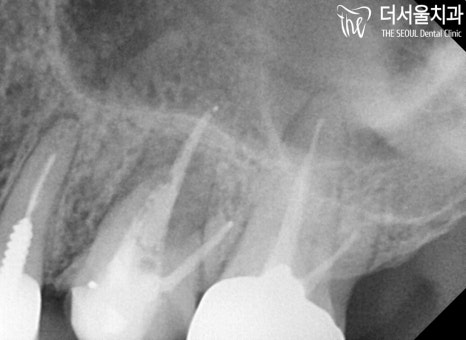

청소가 깔끔하게 되었는지

CT 촬영을 통하여 좀 더 정확히 살펴봅니다.

송파 치과 에서 꼼꼼히 제거해드리며,

텅 빈 공간을 여러번 소독 후,

충전재료로 다시 채워드리기로 했습니다.

이때, 다행스러웠던 것은

포스트라는 것을 하지 않아도 되었다는 것이죠.

그정도로 심하게 약해진 이는 아녀서